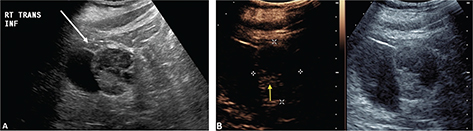

CEUS can be used to follow patients for residual or recurrent tumor with high accuracy. Any residual tumor will be identified as areas of increased enhancement. Absence of blood flow as in Figure 3B confirms complete ablation of the renal tumor. Note that it is not possible to determine if contrast is not utilized in Figure 3A. Figure 4 demonstrates a case where residual tumor (calipers) is present.

Fig 3

Figure 3. Successful ablation. Patient presented for 3-month post-RFA evaluation. (A) B-mode image before the ablation. Large heterogeneous tumor is noted on gray scale examination (arrow). (B) Absence of residual blood flow (arrow) is demonstrated on CEUS examination.

Fig 4

Figure 4. Tumor recurrence/inadequate ablation. Patient presented for CEUS examination 6 weeks after RFA. (A) The B-mode image demonstrates a complex mass (arrow) with solid and cystic components. It is not possible to determine if there is residual tumor. (B) CEUS image demonstrates the tumor (calipers) with residual flow in the posterior part of the tumor (arrow).

Occasionally a complete ablation cannot be obtained. This is often from significant blood flow to the mass or the mass adjacent to the collection system which acts as heat sinks and does not allow for adequate temperature to ablate the tumor. Figure 5 demonstrates a renal mass on the B-mode image (A) and the CEUS image (B). Immediately post-RFA, the B-mode (C) and CEUS (D) demonstrate minimal ablation of the tumor.

Fig 5

Figure 5. Failed ablation. Patient has history of prior left nephrectomy for RCC and presented with right renal mass. (A) Gray scale image of mass (arrow) pre-ablation. (B) CEUS demonstrating increased flow in tumor (arrow) at inferior pole of right kidney. (C) Gray scale image post-RFA of the mass (arrow). (D) CEUS post-RFA demonstrating flow throughout the tumor (arrow), indicating failed RFA.